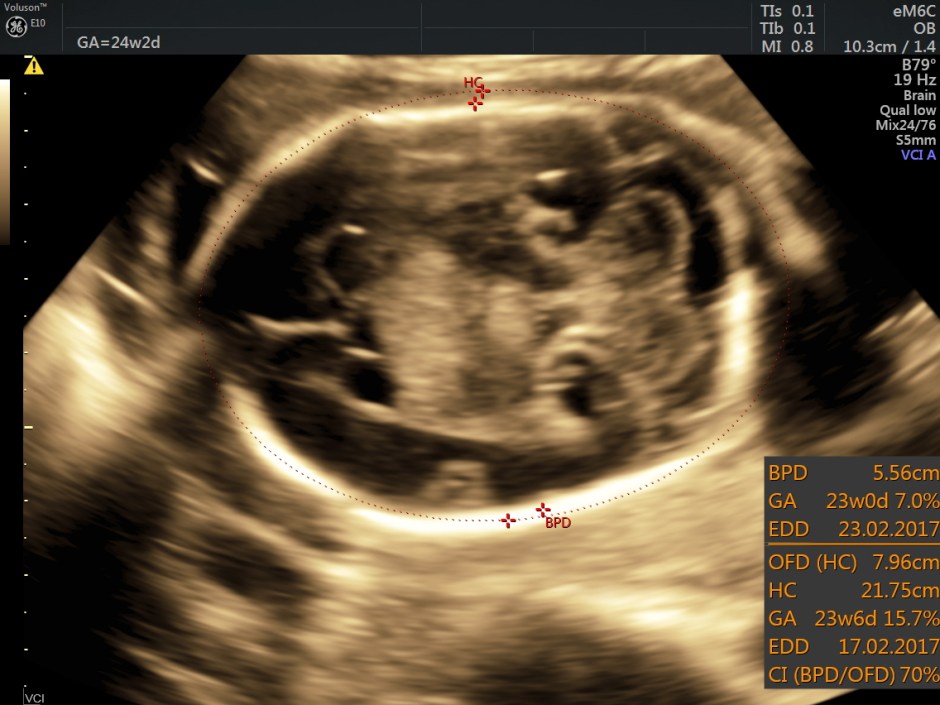

Her BPD ( 6.5 % tile) and HC ( 7 % tile) were less than 10 % tile. Mild ventriculomegaly was seen. ( 11.34 % tile).